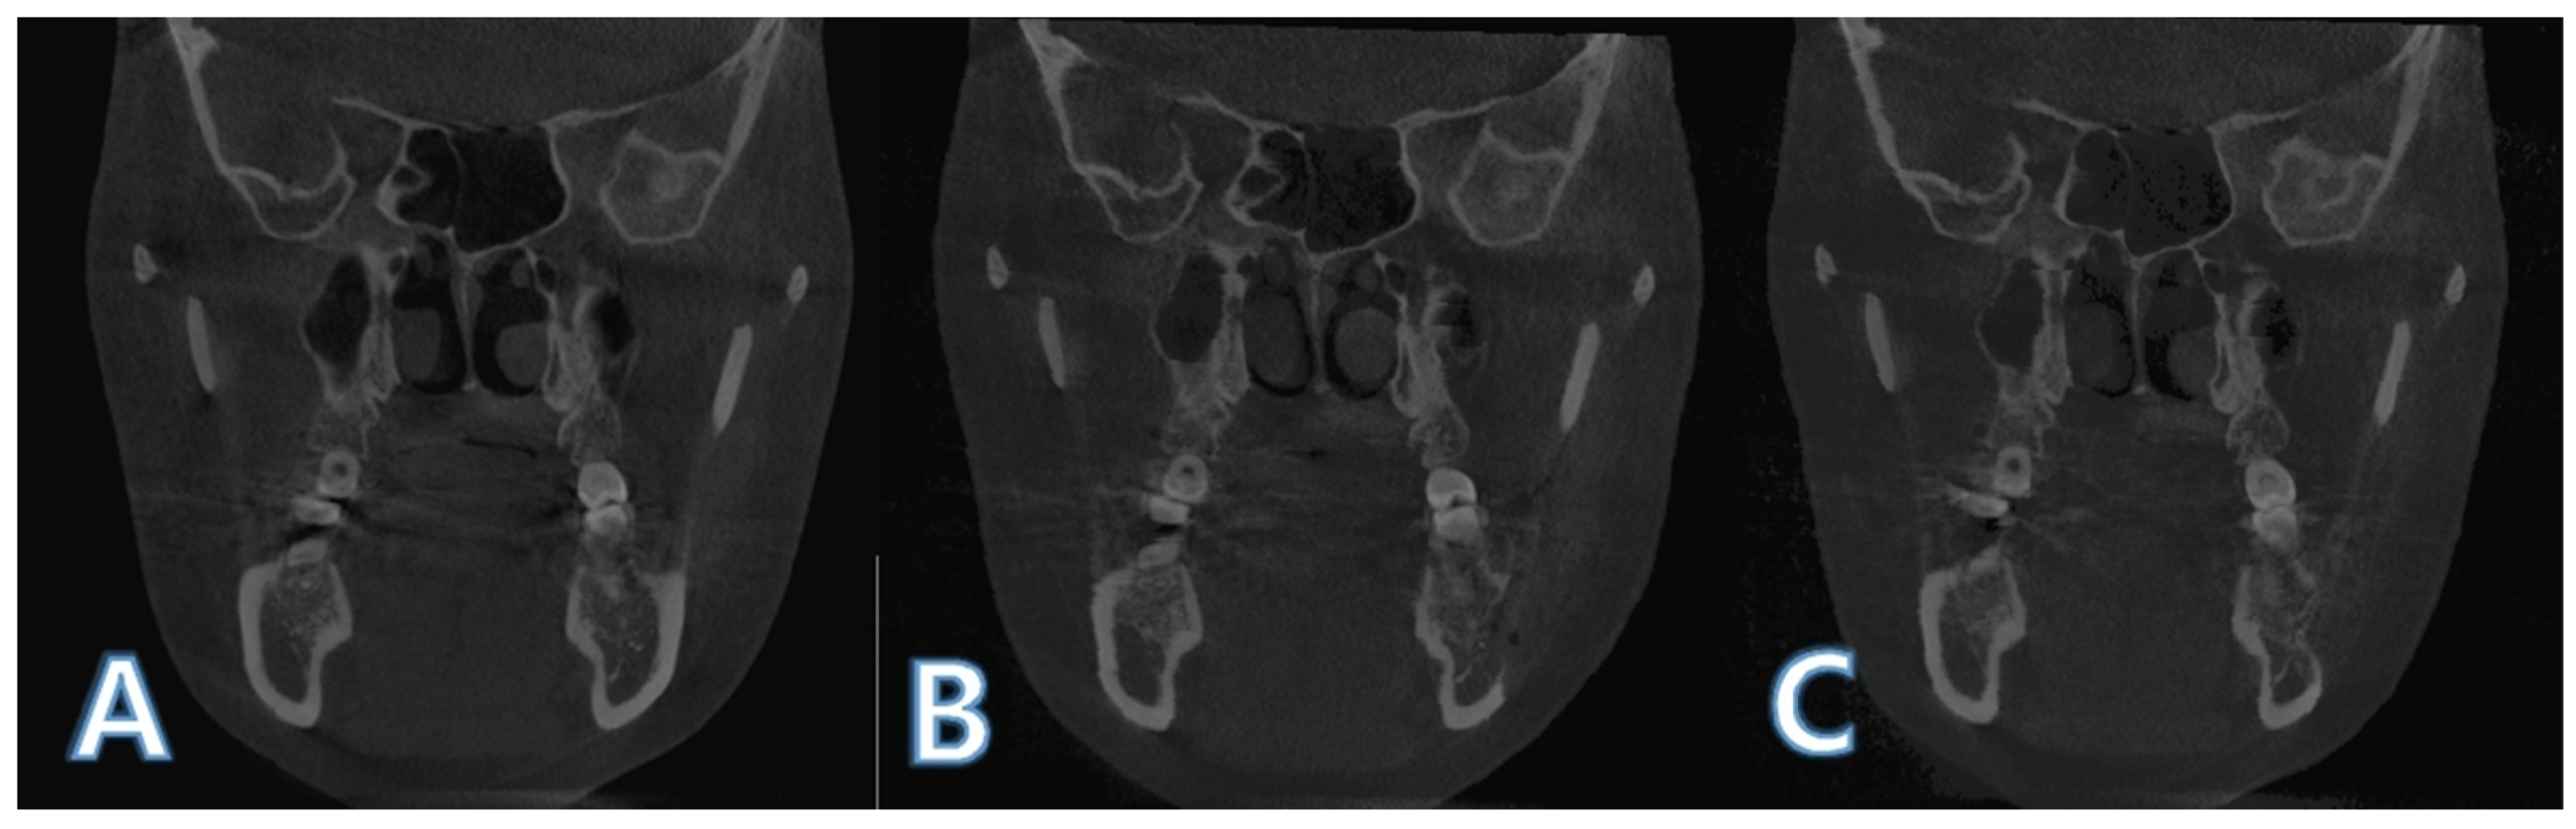

2.2. Boundary Selection of Region of Interest and Mandible Segmentation

2.3. Intensity-Based Registsration Using Segmented Mandible

2.4. Histogram Matching for Pixel Value Comparison

2.5. ROI Image Acquisition and Boundary Separation

2.6. ROI Volume and Mean Pixel Value Calculation